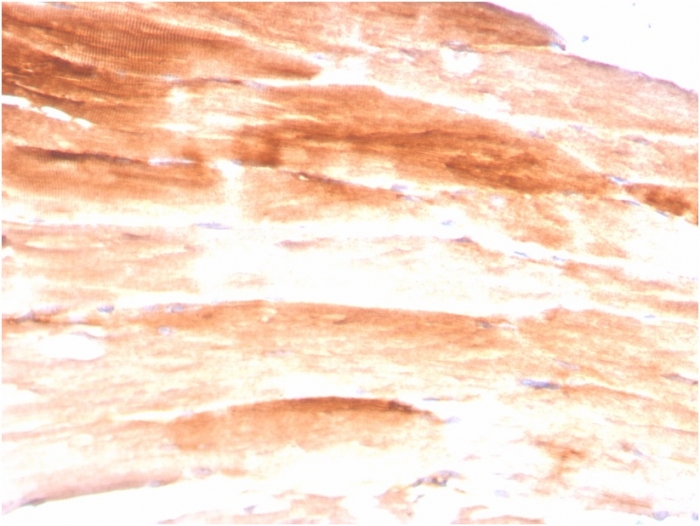

Formalin-fixed, paraffin-embedded human Skeletal Muscle stained with Dystrophin Monospecific Mouse Monoclonal Antibody (DMD/3245).

Dystrophin-glycoprotein complex (DGC) connects the F-Actin cytoskeleton on the inner surface of muscle fibers to the surrounding extracellular matrix, through the cell membrane interface. A deficiency in this protein contributes to Duchenne (DMD) and Becker (BMD) muscular dystrophies. The human dystrophin gene measures 2.4 megabases, has more than 80 exons, produces a 14 kb mRNA and contains at least 8 independent tissue-specific promoters and 2 poly A sites. The dystrophin mRNA can undergo differential splicing and produce a range of transcripts that encode a large set of proteins. Dystrophin represents approximately 0.002% of total striated muscle protein and localizes to triadic junctions in skeletal muscle, where it is thought to influence calcium ion homeostasis and force transmission.